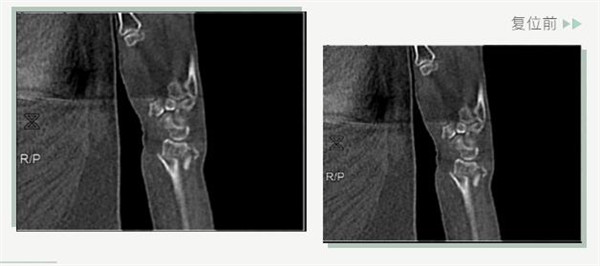

復位前

25日當天,莊阿婆來到危立軍副院長門診,經(jīng)拍片顯示,莊阿婆左橈骨遠端粉碎性骨折,左髂骨至髖臼后緣及恥骨下支骨折??紤]到莊阿婆年紀較大,基礎病較多,難以經(jīng)受手術創(chuàng)傷,傳統(tǒng)手法復位更為合適。推、拽、按、捺……經(jīng)過危立軍副院長一番手法復位后,再次拍片顯示莊阿婆橈骨遠端骨折端復位位置良好,莊阿婆及其家人感到非常滿意。

復位后